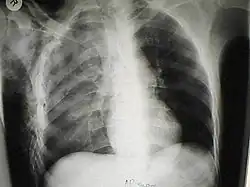

Significant cases of subcutaneous emphysema are easy to diagnose because of the characteristic signs of the condition.[1] In some cases, the signs are subtle, making diagnosis more difficult.[13] Medical imaging is used to diagnose the condition or confirm a diagnosis made using clinical signs. On a chest radiograph, subcutaneous emphysema may be seen as radiolucent striations in the pattern expected from the pectoralis major muscle group. Air in the subcutaneous tissues may interfere with radiography of the chest, potentially obscuring serious conditions such as pneumothorax.[18] It can also reduce the effectiveness of chest ultrasound.[28] On the other hand, since subcutaneous emphysema may become apparent in chest X-rays before a pneumothorax does, its presence may be used to infer that of the latter injury.[13] Subcutaneous emphysema can also be seen in CT scans, with the air pockets appearing as dark areas. CT scanning is so sensitive that it commonly makes it possible to find the exact spot from which air is entering the soft tissues.[13] In 1944, M.T. Macklin and C.C. Macklin published further insights into the pathophysiology of spontaneous Macklin's Syndrome occurring as a result of a severe asthmatic attack.